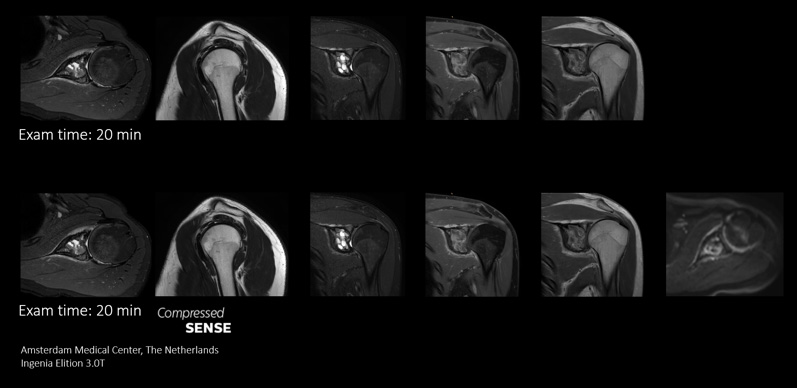

Compressed SENSEを使用することにより、同じMR検査枠でより多くの情報を取得できる高い柔軟性が得られます。また、高速化によって、機能的シーケンスなど特殊なシーケンスをさらに追加してより有用な診断情報を取得することができます。

このケースでは、同じ検査枠内にシーケンスを追加して、診断能を向上させています。ここでは、従来のTSEシーケンスに加えて、診断に役立つ追加の情報が含まれたDWIシーケンスを同じ検査枠内に追加しています。

Compressed SENSEを使用した高速化スキャンによって時間を節約できるので、高画質の画像を取得して診断能を高めるためのシーケンスを追加できます。

福島沙知氏、放射線技師、倉敷中央病院